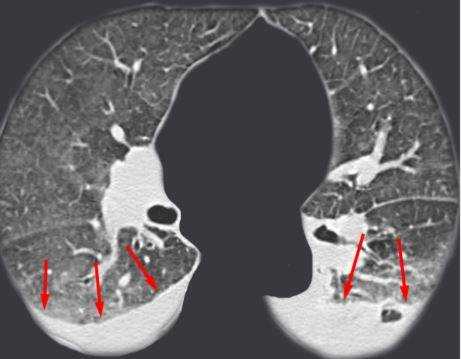

Метастазы чаще всего представлены узловыми образованиями в легочной ткани вне строгой связи с легочными артериями или венами. Для них характерны следующие КТ-признаки:

Вторичные узлы гематогенного характера чаще всего имеют ровные края, четкие контуры и однородную структуру. Возможны изменения структуры опухоли вследствие кровоизлияния в паренхиму, обызвествлений, некроза центральной части узла, а также рубцов. Края узла могут стать нечеткими, расплывчатыми, если опухоль провоцирует отек легочной паренхимы, либо «лучистыми», если имеет место опухолевый лимфангиит.

Гематогенные метастазы наиболее часто локализуются в периферических отделах легких, вдали от крупных сосудисто-бронхиальных пучков, вблизи плевральной оболочки. При множественных поражениях гематогенного характера наблюдается тенденция к увеличению количества очагов в направлении «сверху-вниз». Чаще гематогенные метастазы расположены хаотично, вне четкой связи с бронхами и видимыми легочными сосудами. Практически не бывает такого, чтобы гематогенные вторичные узлы находились только с одной стороны, или занимали только одну долю или сегмент. При наличии такого распределения в первую очередь нужно думать о туберкулезе (верхние доли), множественных абсцессах и т. д.

Лимфогенные метастазы проявляются увеличением лимфатических узлов средостения в сочетании с мелкоочаговой диссеминацией с очагами до 2-3 мм в диаметре вблизи плевры и в междольковых перегородках, а также по ходу бронхов и сосудистых пучков.